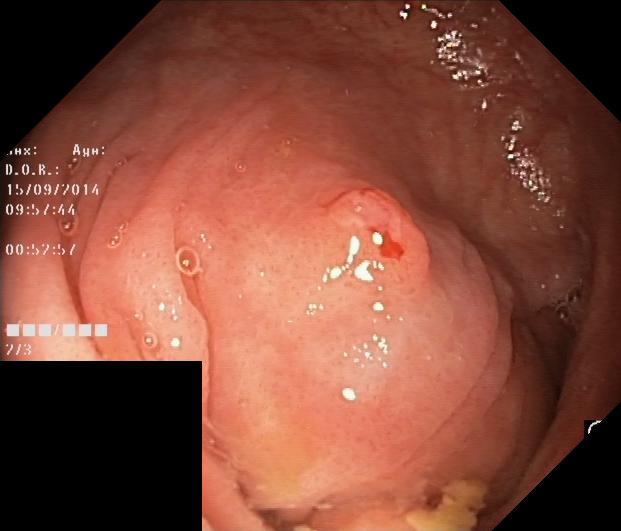

KVASIR-SEG KVASIR-SEG is an endoscopic dataset specifically created for pixel-level segmentation of colonic polyps[34], and it was featured as part of the MediaEval 2020 benchmarking challenge. The dataset includes 1,000 gastrointestinal polyp images, each paired with corresponding segmentation masks. These masks were carefully annotated and validated by board-certified gastroenterologists to ensure high diagnostic accuracy [34]. In this study, we randomly divided the dataset into 700 images for the training set, 100 images for the validation set, and 200 images for the testing set, along with their respective labels. For datasets containing validation datasets, we only validate the performance of the model during training after each epoch and iteratively save the weights that give the best performance on the validation set. When model training finishes, we reload the weights from the best-performing model for testing on the unseen test set. Otherwise, the testing set is used as the validation set instead. Some examples and corresponding labels can be seen in Figure 6.